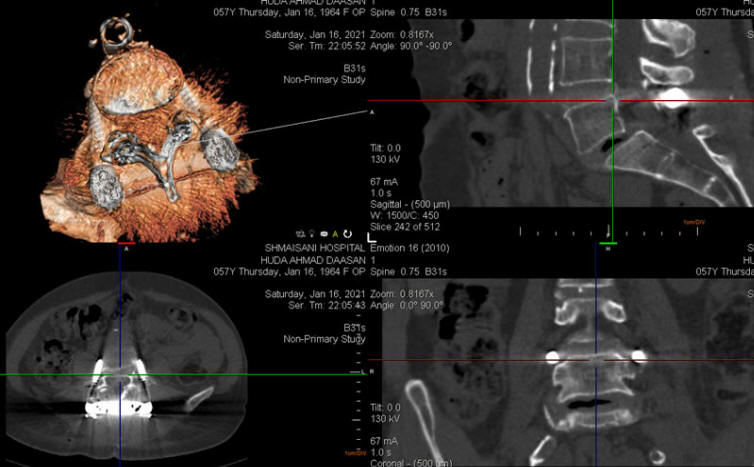

17-JANUARY-2021  HUDA AHMAD DAASAN  57 YEARS  UNACCEPTABLE UPPER SCREWS LOCATION AFTER FIXATION DONE 3 DAYS AGO.

The patient power of the lower limbs improved, but she is telling that the right gastrocnemius muscle is tight. Control CT-scan of the constructs performed the evening of 16-January-2021 showed unacceptable both upper screws at the level of L5. The sacral screws are acceptable. It was decided to explore the wound redirect the upper screws.

The left upper screw far-lateral.

The right upper screw far lateral and above the pedicle.

The upper screws are far lateral.

X-ray reconstruction using ORS Visual program

Post correction performed 18-January-2021